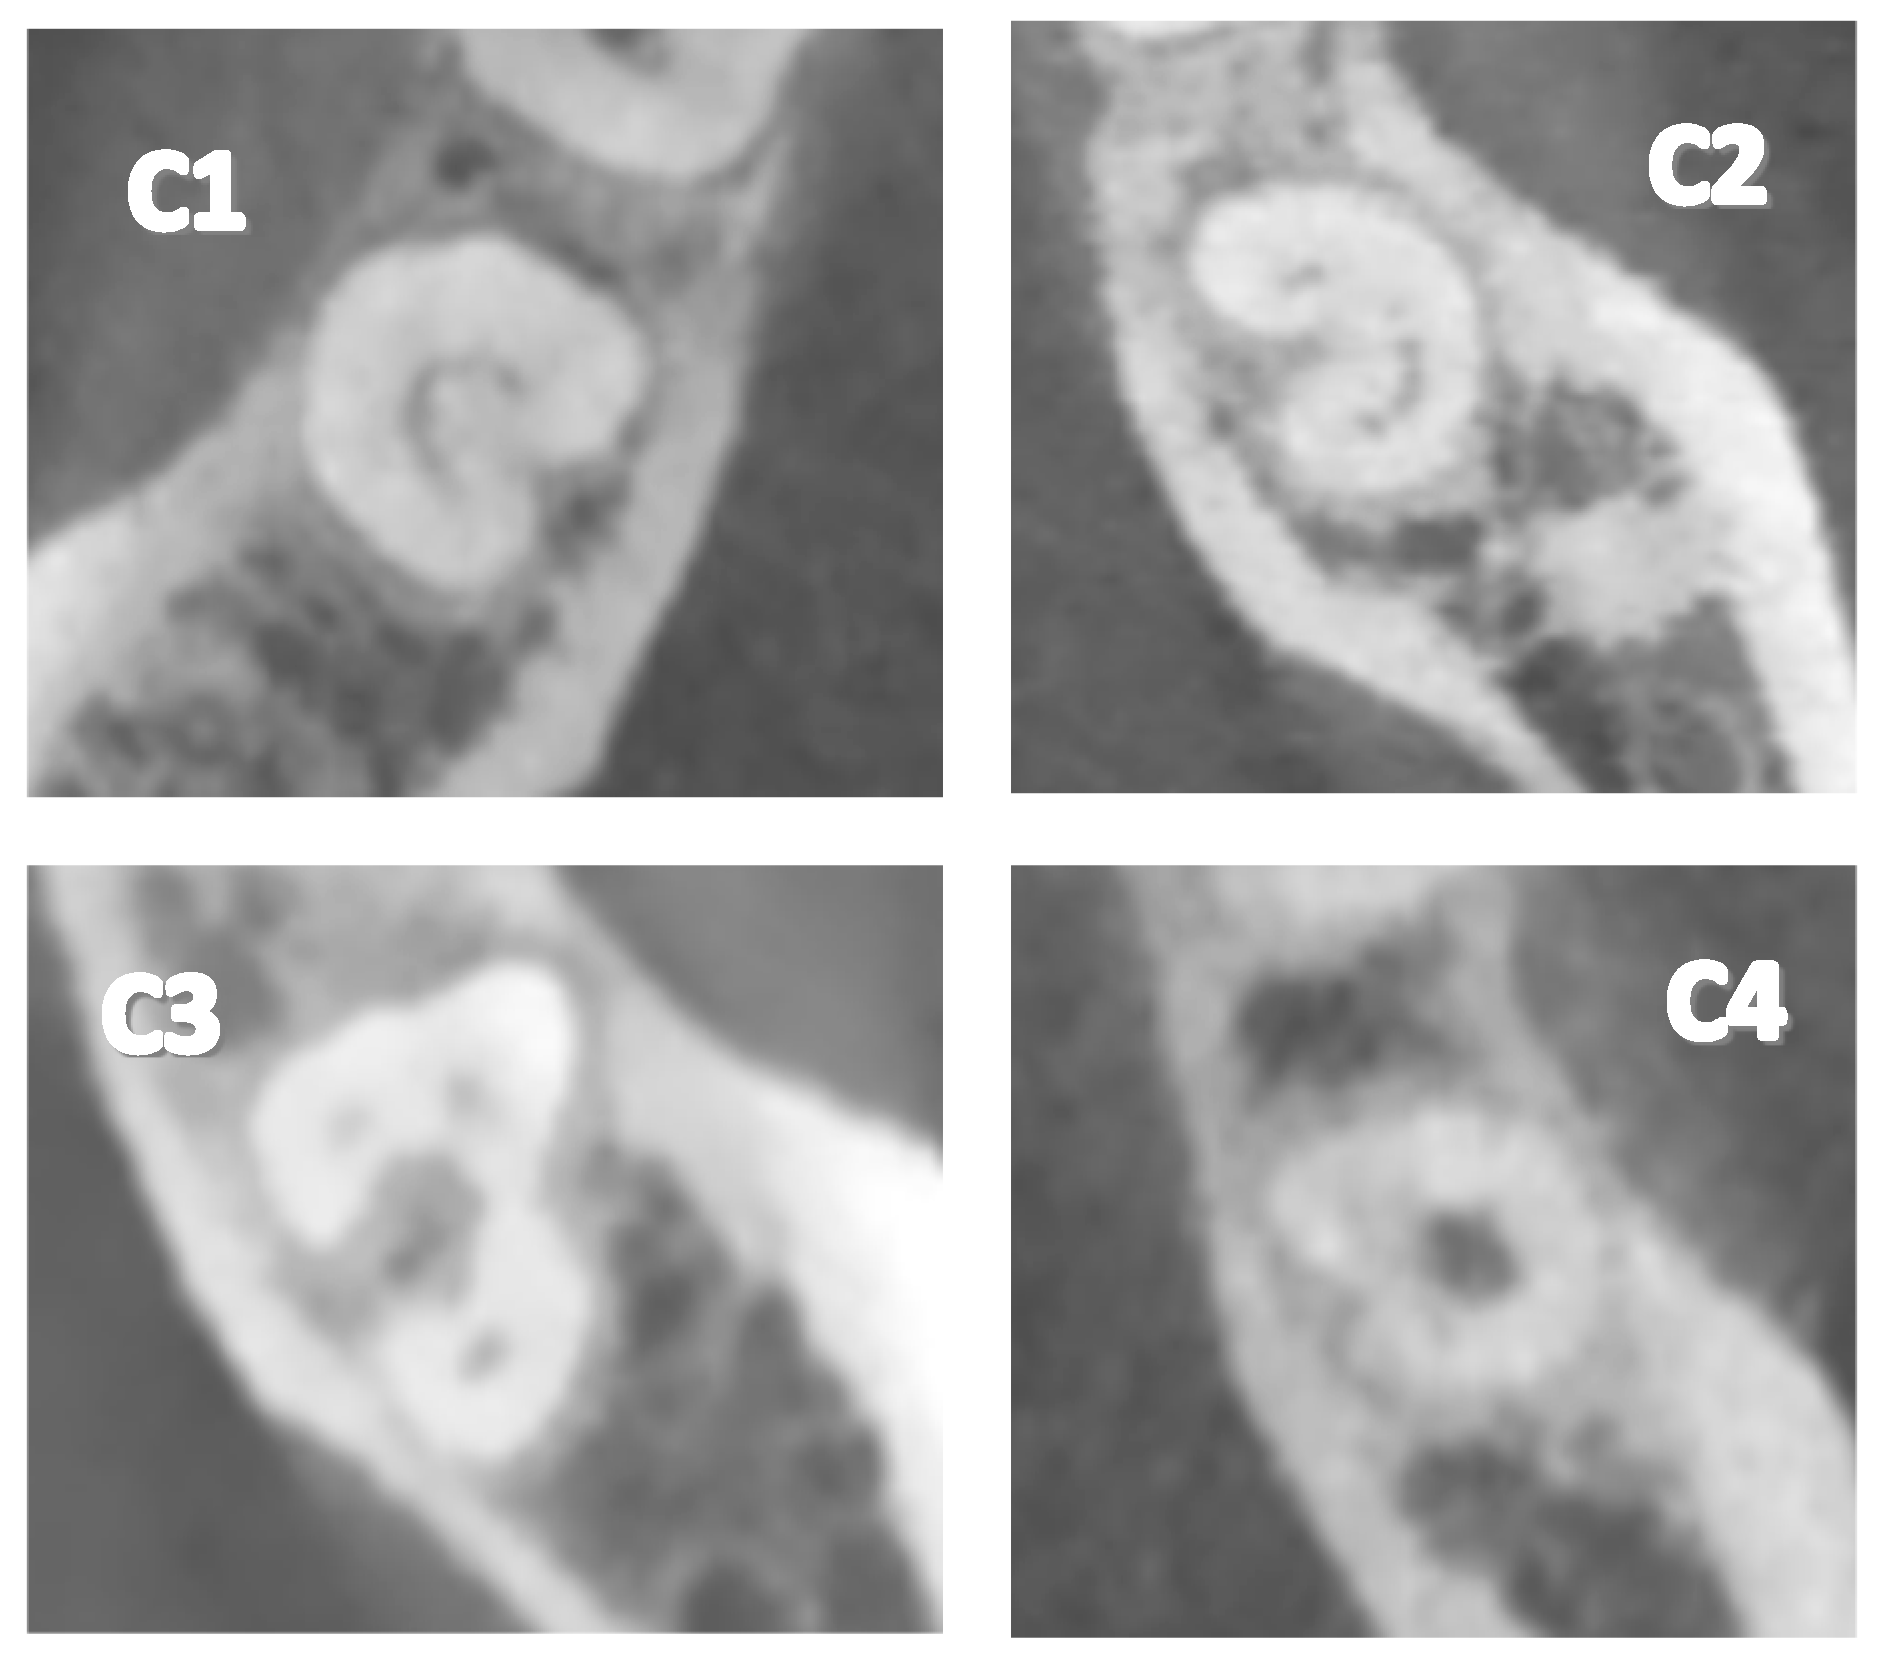

- Type 1 (C1): The C-shape is observed continuously without interruptions or separations.

- Type 2 (C2): The C-shape is observed interrupted, resembling a semicolon, but angles α and β are less than 60°.

- Type 3 (C3): Two or three separate canals are observed, with both angles α and β being less than 60°.

- Type 4 (C4): A single round or oval canal is observed in the cross-section.

| C1 | 42 | 26.3% |

| C2 | 63 | 39.3% |

| C3 | 30 | 18.8% |

| C4 | 25 | 15.6% |

| C5 | 0 | 0% |